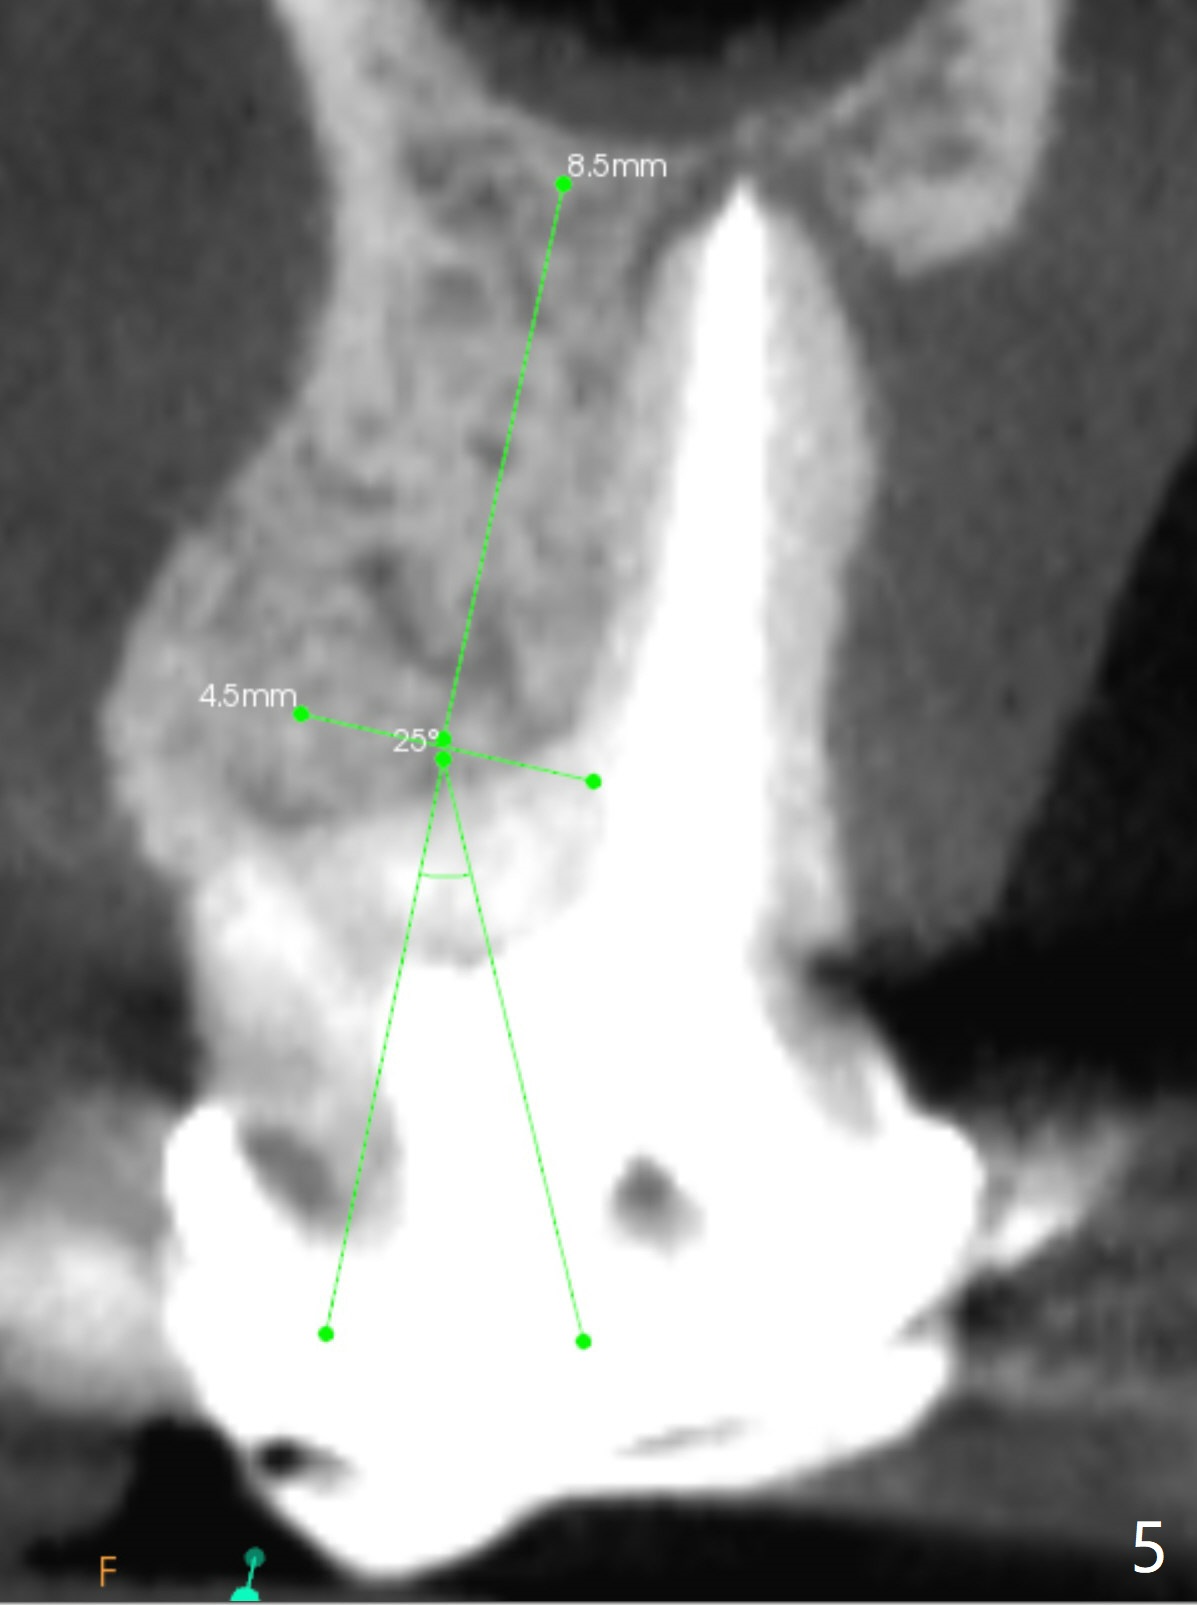

A 52-year-old woman has had chronic abscess associated with the tooth #3. The palatal root is exposed (Fig.1 P), suggesting root fracture. The apex of the mesiobuccal root seems to stick out of the buccal plate (Fig.2 *). The root canal filling is incomplete in the distobuccal root (Fig.3 *). The tooth appears to have guarded prognosis. Extraction and immediate implant is apparently a better option (Fig.4,5). It would be safer to start osteotomy in the middle of the remaining septum (Fig.6, as compared to Fig.5). After sinus lift with PRF membrane (Fig.7 yellow curved line) and implant placement (green), another piece of PRF membrane will be placed against the palatal wall of the socket, followed by bone graft (red circles) and a 25-degree angled abutment (pink).